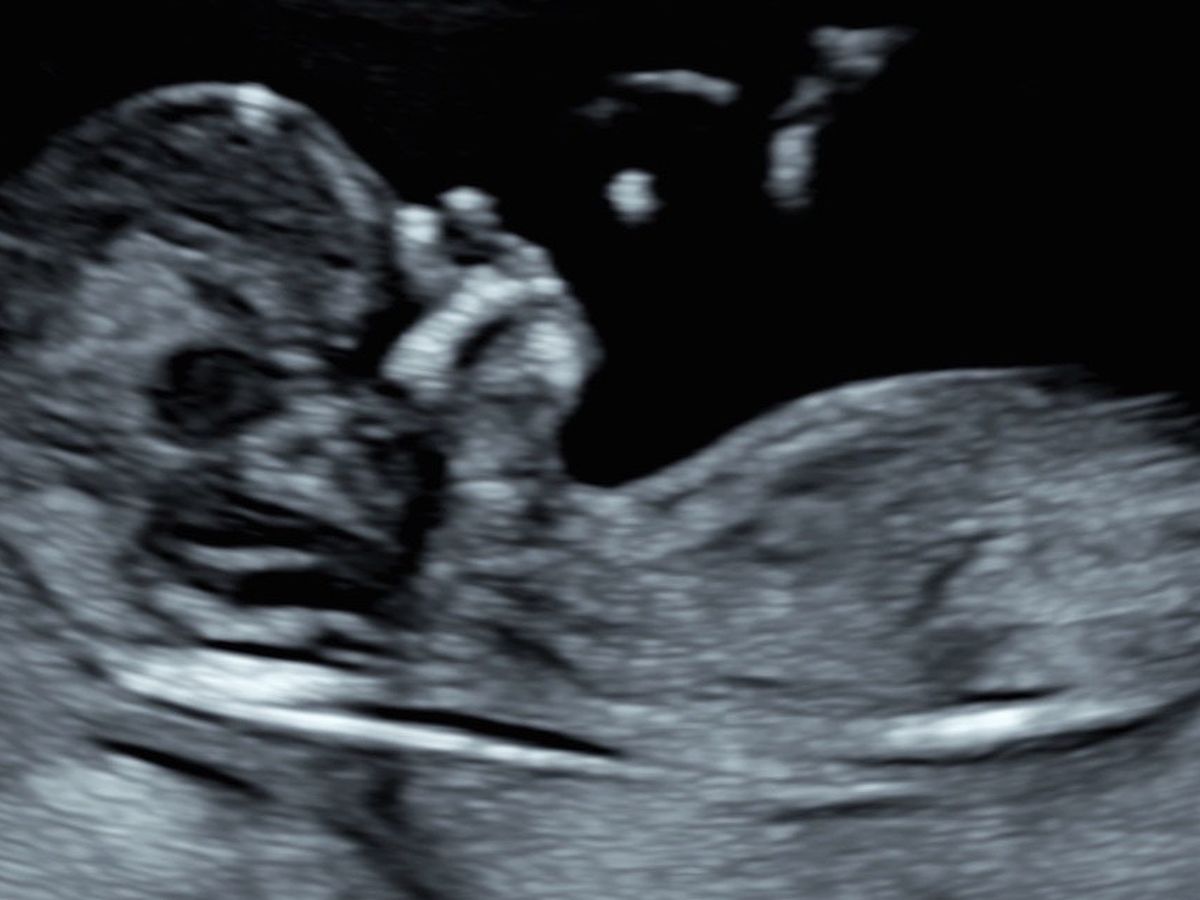

This in an uncomfortable post for me but extremely necessary and important. During one of my many appointments today for the loss of our baby, the social worker brought up what we wanted to do with the remains. She explained to me that if I wanted back my son’s remains that I had to choose a funeral home. That I had to choose between cremation or a burial spot. If not I wouldn’t be able to get him back since I was already in my 2nd Trimester. And either was going to cost money. This whole process is racking up costs that I can’t currently afford. From the bottom of my heart I am asking anyone who can , to please donate so I can bring him home. This is the hardest thing I’ve ever had to go through. I just feel like there’s so much piling up onto of my grief.